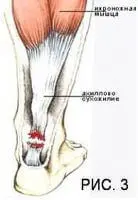

Чаще место разрыва сухожилия находится на расстоянии 2—5 см от места прикрепления его к пяточной кости, что обусловлено наиболее слабым кровоснабжением данного участка сухожилия. (Рис 3).